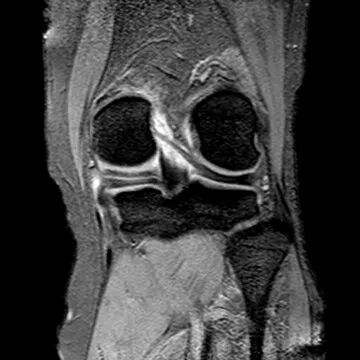

半月板撕裂:桶柄状撕裂(双前角征)

桶柄状撕裂(双后交叉韧带征)

桶柄状撕裂:双前交叉韧带征